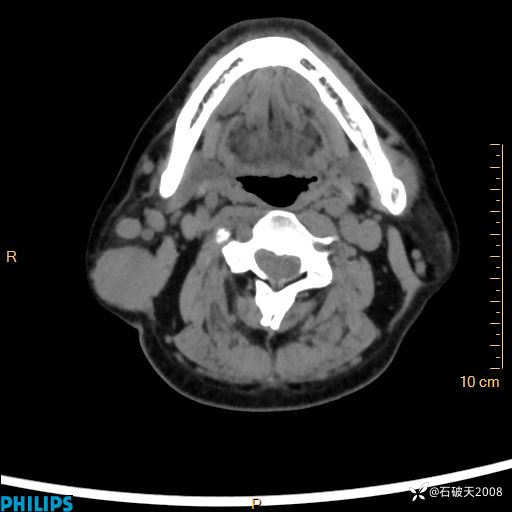

动脉期